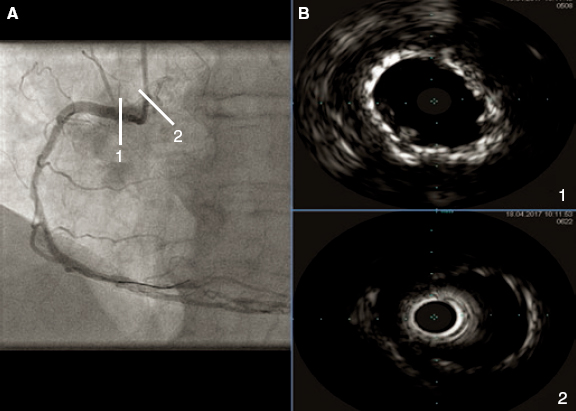

The angiographic results were good (figure 5A) and the intravascular ultrasound examination conducted showed the double layer of stents at ostium level with good stent apposition and expansion (figure 5B1) and the stent deployed protruding into the aorta showed wide overexpansion (figure 5B2).

Figure 5. A: final angiographic result. B1: intracoronary ultrasound image showing the double layer of stents at ostium level with good stent apposition and expansion. B2: intracoronary ultrasound image showing the stent implanted in the first place, protruding into the aorta, and showing wide overexpansion.